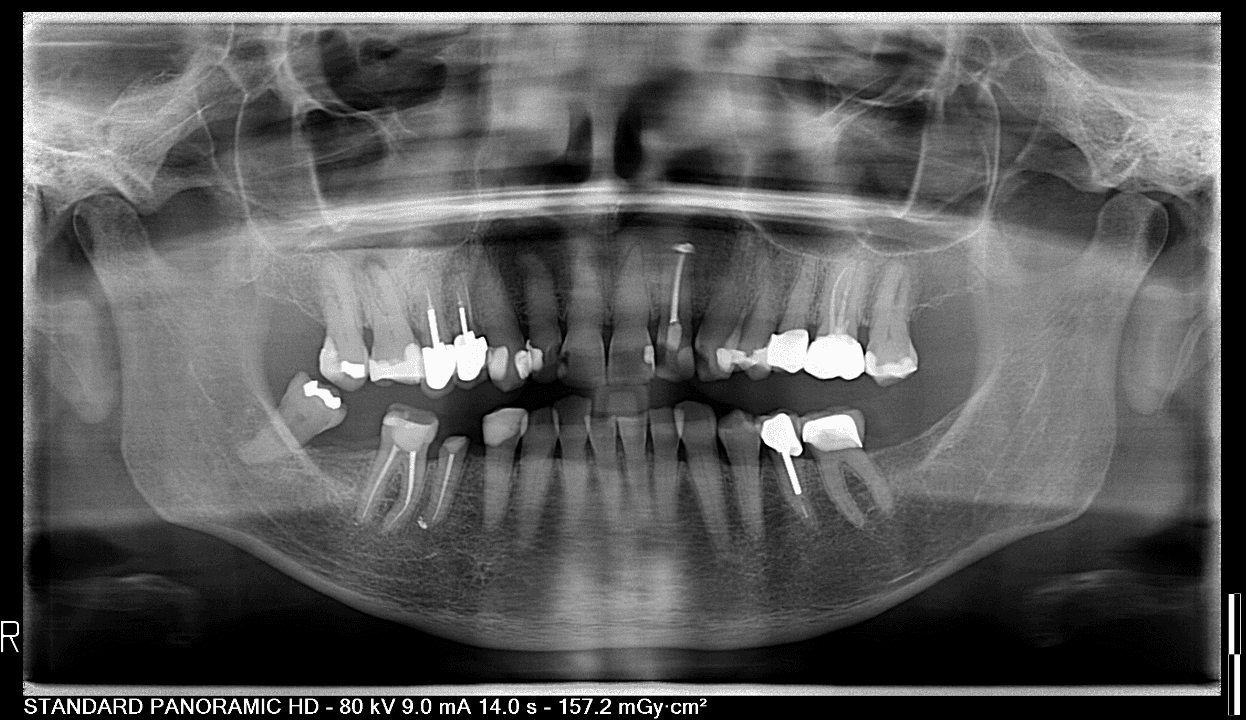

Panoramisch overzicht: Voor een compleet beeld van je kaken, neusholtes en wortelpunten.